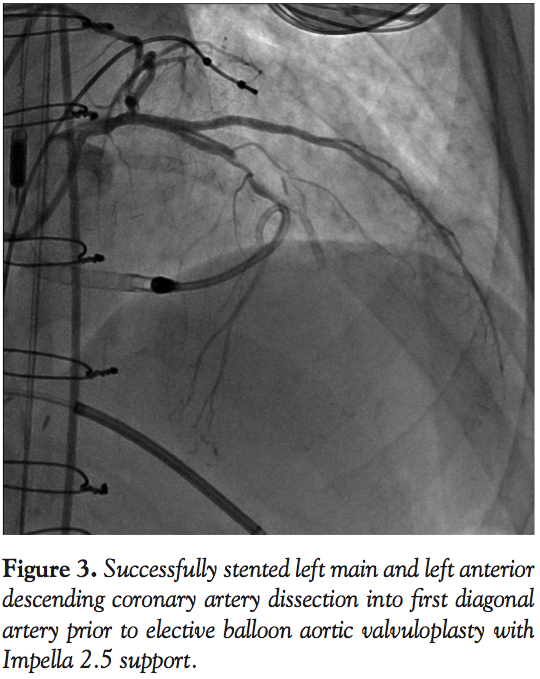

Cardiac catheterization from the right common femoral artery demonstrated that all 3 grafts were patent. A diseased non-bypassed diagonal artery was identified as a PCI target (Figure 1A) with the goal of improving left ventricular function. After angiography demonstrated adequate femoral artery dimensions, access to the left common femoral artery was obtained and the aortic valve was crossed using the standard technique with an Amplatz left (AL2) catheter. Baseline aortic valve gradient was 43 mm Hg. An Impella 2.5 (Abiomed) was

placed. Baseline cardiac output and capillary wedge pressure were 4.5 L/min and 25 mm Hg, respectively. Two minutes after placement of the Impella 2.5, these parameters improved to 6.0 L/min and 18 mm Hg, respectively and systemic blood pressure as measured in the proximal aorta improved to 110-120/55-70 mm Hg. The 90% proximal stenosis of the first diagonal artery was then successfully treated by PCI with a 2.5 x 28 mm drug-eluting stent (Figure 1B). Subsequently, a spiral left main (LM) guide dissection was identified (Figure 2). The patient remained hemodynamically stable. The protected left anterior descending (LAD) artery and unprotected diagonal were wired and PCI from the diagonal artery into the proximal LAD and the LM with 2.5 x 28 mm and 3.5 x 15 mm stents was successfully undertaken (Figure 3). The aortic valve was then crossed with a second wire and successful BAV with a 20 x 6 mm Z-Med II Balloon (NuMED, Inc) was performed (Figure 4). Rapid pacing of the right ventricle was not necessary. The patient remained hemodynamically stable throughout the whole procedure. The Impella was left in for 24 hours before being weaned and removed. The patient was discharged on home inotropes. At 6-week follow-up exam in the heart transplant clinic, he remained stable with NYHA III symptoms and was listed for heart transplant as a United Network of Organ Sharing (UNOS) Status IB. At 8 weeks, he underwent successful heart transplant surgery.